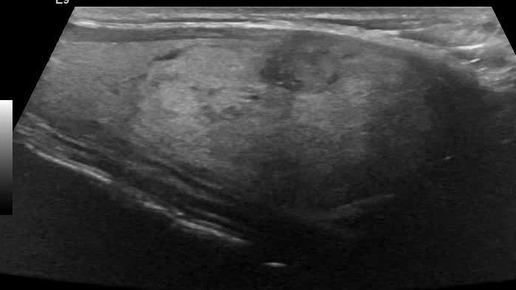

Видео к статье "Стратификация узлов щитовидной железы. TI-RADS-4" https://dzen.ru/a/ZwNx-uQp-Sfk6L46

Ультразвуковые находки от врача УЗД Зорина Я.П.